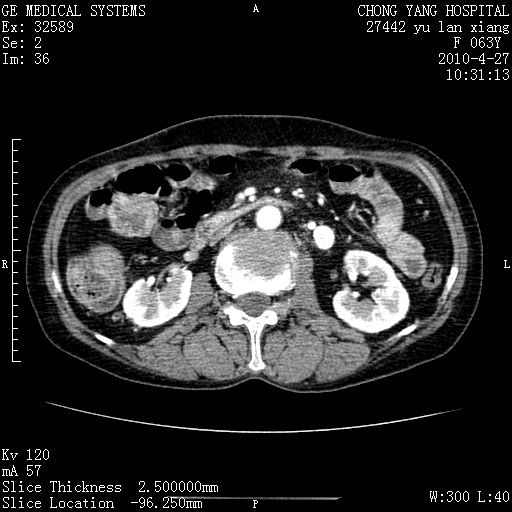

标题: CT26066:F63Y 上腹正中压痛半月,CA199:7400u/ml,MR示胰腺炎伴 [打印本页]

胰腺癌侵犯腹腔动脉干-分支、胃壁、左侧膈肌伴胰周及腹膜后淋巴结转移、胆囊切除术后。

胰腺癌侵犯腹腔动脉干-分支、胃壁、左侧膈肌伴胰周及腹膜后淋巴结转移、胆囊未显影。